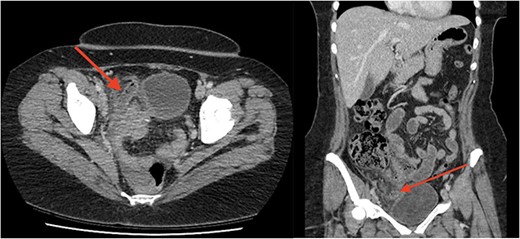

A woman in her 40s presented to a nearby district hospital with 1 day of abdominal pain. Pain was initially a dull ache in her right upper quadrant radiating to her back, she had no other associated symptoms. After review, she was discharged with a referral for an abdominal ultrasound to look for a biliary cause. Later that afternoon, pain became severe, migrating to her lower abdomen and she represented. There were no bowel or urinary symptoms. The patient was usually fit and well and took no regular medications. In her past, she had severe menorrhagia and dysmenorrhea for which she had an endometrial ablation, and later a transvaginal total hysterectomy. She described her pain as identical to the severe pain she used to have with menstruation. Her white cell count was 20.4 × 109 cells/L and C-reactive protein 378.9 mg/L; biochemistry and liver function tests were otherwise unremarkable. A CT was performed that revealed a 14-mm appendix with significant surrounding fat stranding and a small volume of free fluid (Fig. 1). There was no free gas or organized collection. The patient was then accepted for transfer to our hospital’s emergency department. Upon arrival, she was haemodynamically stable and afebrile, her abdomen revealed generalized lower abdominal tenderness with focal peritonism in the right iliac fossa.

Axial (a) and coronal (b) images from portal-venous phase CT of the abdomen and pelvis demonstrating acute appendicitis. Arrow to inflamed, enlarged appendix.